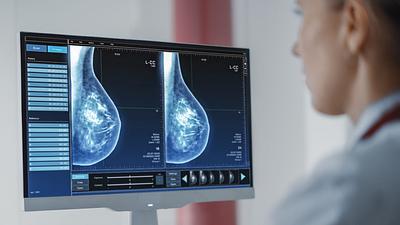

IA antecipa risco de câncer de mama por até cinco anos

Modelo de inteligência artificial analisa mamografias para avaliar risco do desenvolvimento da doença. Técnica pode ajudar a identificar casos não detectados pelo exame tradicional.